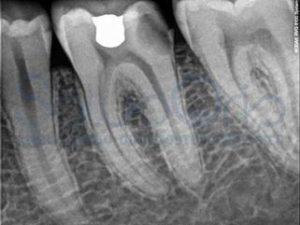

Questi acidi cominciano a sciogliere i cristalli di calcio e fosfato all’interno di un dente. In tale zona potrebbe comparire una macchia bianca sullo smalto.

In questa fase, il dente può essere riparato con l’aiuto di sostanze contenenti fluoro.Se non trattata, la lesione peggiorerà, potendo distruggere tutto lo smalto, la dentina, fino ad arrivare alla polpa del dente.